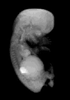

Carnegie Stage 23 (56 post-ovulatory days)

Most embryos at stage 23 are approximately 56-57 postovulatory days old and measure 23-32 mm in length. Distinguishing criteria for this stage include fusion of the eyelids at the medial and lateral margins, clear distinction of the subdivisions of the upper and lower limbs, the forearms appear at or above the level of the shoulders, the superficial vascular plexus of the head is very close to the vertex, and the external genitalia are well developed but not always sufficiently to distinguish the embryo's sex.

(NOTE: These specimens are late stage 23.)